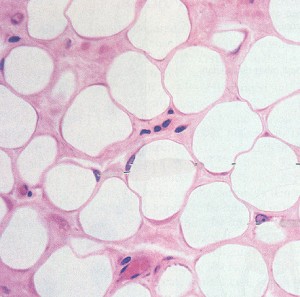

Клетки жировой ткани

Жировая ткань состоит из различных клеточных популяций. Первая популяция – это непосредственно жировые клетки или адипоциты. Все остальные популяции клеток находятся в “стромально-сосудистой” фракции жировой ткани. Иными словами, мы имеем две фракции жировой ткани: 1) фракция жировых клеток (популяция адипоцитов) и 2) стромально сосудистую фракцию (гетерогенную клеточную популяцию со всеми видами и типами клеток). Стромально-сосудистая фракция включает в себя клетки кровеносных сосудов (клетки эндотелия), стволовые клетки, молодые, не сформированные адипоциты (преадипоциты), фибробласты и т.д.